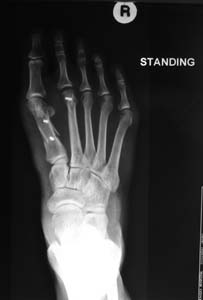

A scarf osteotomy was performed. It involved cutting the 1st metatarsal bone using a Z-cut and displacing the toe laterally.